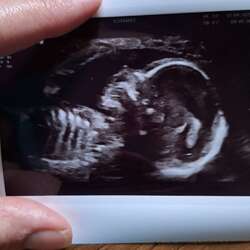

Vannacht heel slecht geslapen, ik had een hele pijnlijke steek in mijn linkerzij, kon het niet goed plaatsen. Maar was wel angstig en onrustig. Nu is het wat minder maar er spoken dan rare dingen door je hoofd als blindedarm of buikvlies… ik hoop dat met mn kleintje alles goed gaat. Komende week de 13 weken echo.